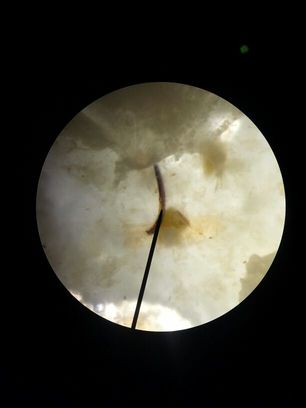

foto microscopio

hola buenas no entiendo muxo pero qeria saber vuestra opinion de qe se ve en esta foto gracias.

IMG-20130212-WA0015.jpg (9.45 KiB) Visto 1112 veces